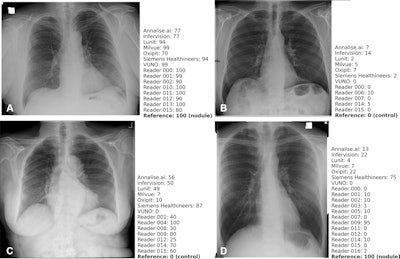

Example chest x-rays from a public test set illustrate algorithm and reader similarities to and discrepancies from the reference standard. A specialized radiologist determined the reference standard score (0, no nodule present; 100, one or more nodules present), and algorithms and human readers provided a probability score between 0 and 100 for each patient of the likelihood that the patient was a nodule case. (A) Radiograph in a man (age, 72 years) with a nodule present (reference standard score, 100) shows a true-positive result based on the average algorithm scores. (B) Radiograph in a man (age, 68 years) without a nodule present (reference standard score, 0) shows a true-negative result based on the average algorithm scores. (C) Radiograph in a woman (age, 64 years) without a nodule present (reference standard score, 0) shows a false-positive result based on the average algorithm scores. (D) Radiograph in a man (age, 37 years) with a nodule present (reference standard score, 100) shows a false-negative result based on the average algorithm scores. Corresponding lateral images and CT scans (when available) for these patients are presented in Figure S2 (supplementary data). The images shown in this figure were part of a public subset and not part of the set on which metrics are reported, which remains confidential for reevaluation in the future. Algorithm scores provided for the images are raw, uncalibrated scores and cannot be directly compared to each other; they are provided for indicative purposes only. Image and caption courtesy of Radiology.